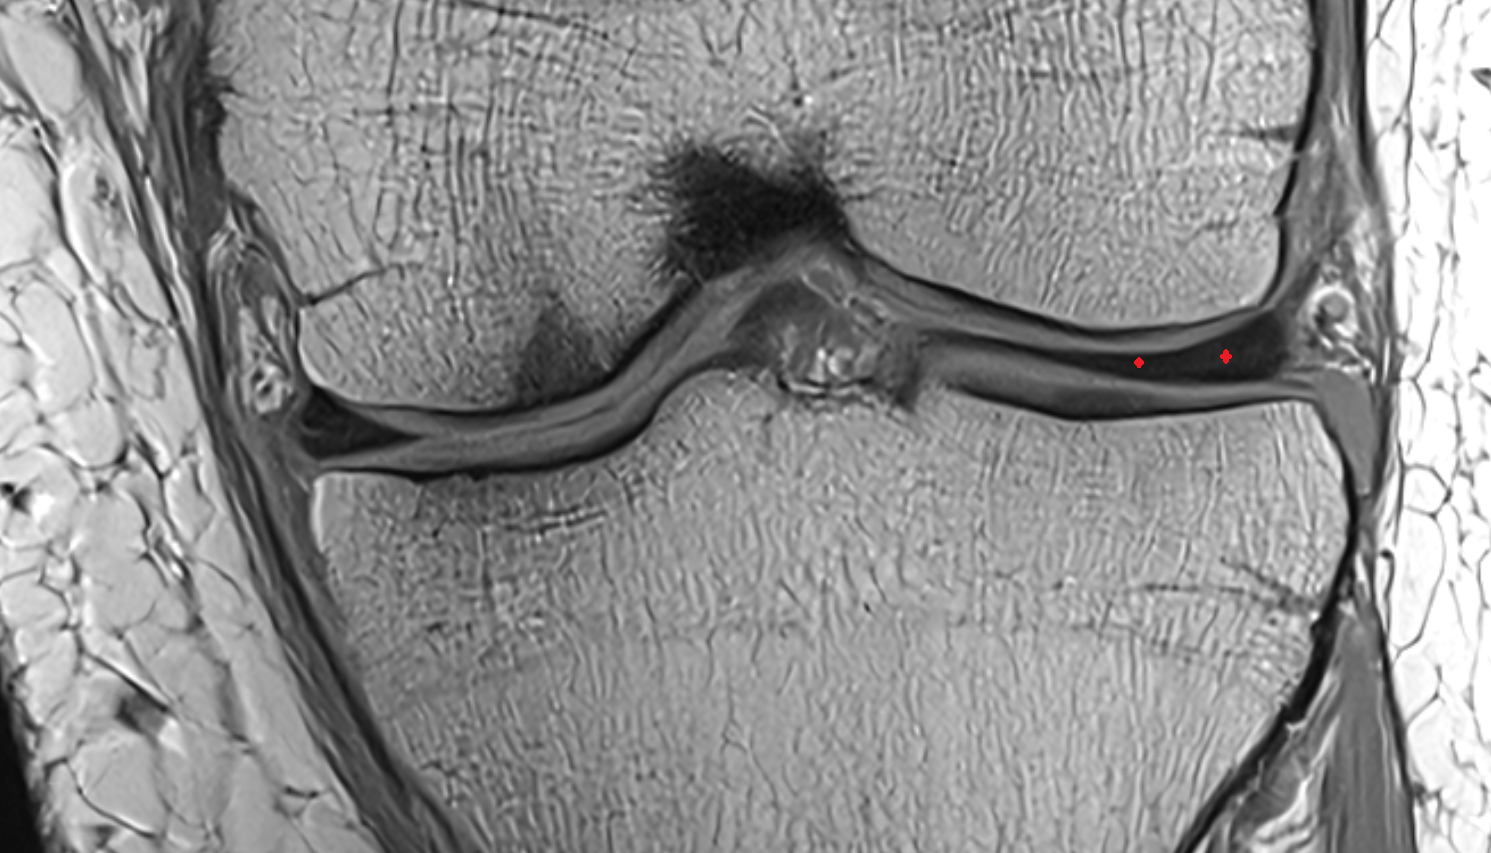

- Medial meniscus

- Lateral meniscus

- Anterior horn of medial meniscus

- Posterior horn of medial meniscus

- Body of medial meniscus

- Anterior root of medial meniscus

- Posterior root of medial meniscus

- Anterior horn of lateral meniscus

- Posterior horn of lateral meniscus

- Body of lateral meniscus

- Anterior root of lateral meniscus

- Posterior root of lateral meniscus

- Knee Joint